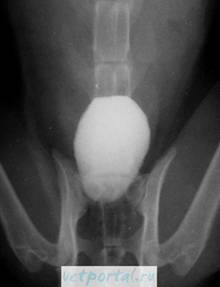

На нисходящей цистограмме при выполнении экскреторной урографии может быть виден дефект наполнения, обусловленный опухолью мочевого пузыря. Одновременно этот метод исследования дает представление об анатомических изменениях и функциональной способности почек и мочеточников, динамике опорожнения почечной лоханки и мочеточников и позволяет оценить уродинамику верхних мочевых путей. При сдавлении интрамурального отдела мочеточника опухолевым инфильтратом и нарушении оттока мочи из верхних мочевых путей с помощью экскреторной урографии можно выявить расширение мочеточника и чашечно-лоханочной системы почек (уретерогидронефроз), а иногда и отсутствие функции этого органа.

Кроме нисходящей цистограммы, получаемой при выполнении экскреторной урографии, иногда приходится прибегать и к восходящей (ретроградной) цистографии, для чего мочевой пузырь наполняют жидким рентгеноконтрастным веществом с помощью введенного в мочевой пузырь катетера. На ретроградной цистограмме более четко выявляется изображение опухоли мочевого пузыря, а также и внутрипузырно расположенная доброкачественная гиперплазия предстательной железы. На восходящей цистограмме при опухоли мочевого пузыря можно определить дефект наполнения. Однако при опухоли незначительных размеров контрастное вещество может прикрывать ее, и тога опухоль не видна. Иногда этот метод исследования позволяет выявить пузырно-мочеточниковый рефлюкс, возникающий вследствие нарушения замыкательного аппарата устья мочеточника из-за инфильтрации стенки мочевого пузыря или сдавления устьев аденоматозными узлами при сочетании опухоли мочевого пузыря с доброкачественной гиперплазией предстательной железы.

Для выявления небольших опухолей мочевого пузыря выполняют осадочную цистографию, которую осуществляют введением в мочевой пузырь через резиновый катетер сначала 50-100 мл 10-15% суспензии сульфата бария. Затем больному рекомендуют в течение 40-60 мин менять положение тела для лучшего контакта препарата с ворсинками опухоли и слизистой оболочки мочевого пузыря. После этого мочевой пузырь опорожняют от сульфата бария, промывают, и через катетер вводят 100-150 мл кислорода. Метод позволяет получить четкое изображение опухоли мочевого пузыря, так как на измененной поверхности опухоли барий задерживается, а с нормальной слизистой оболочки мочевого пузыря полностью смывается. Осадочная цистография особенно ценна при папиллярных опухолях с длинными ворсинками, тогда как при эндофитных опухолях она малоинформативна.